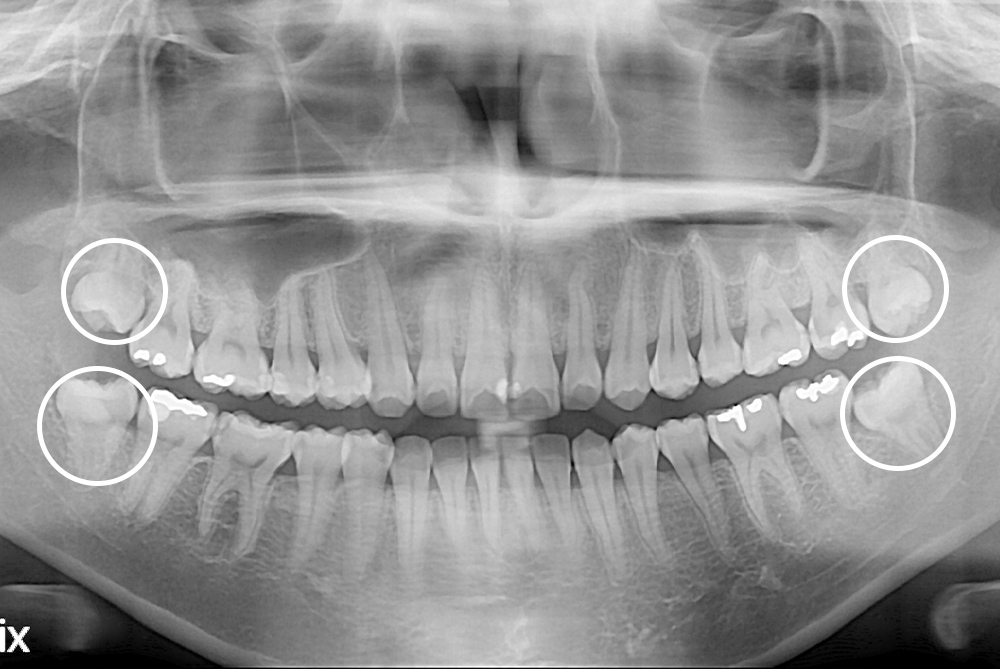

[사랑니] 매복 사랑니 발치

치료전 : 2020-08-07